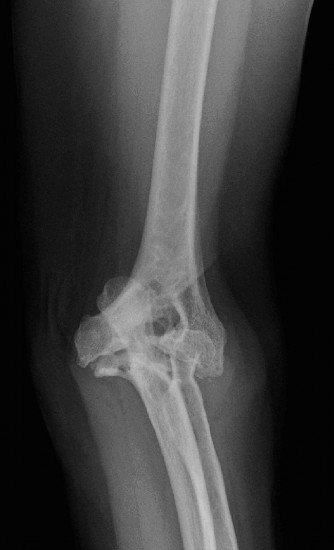

Understand common complications associated with performing surgery for scapulothoracic bursitis? CASE 33 A 42-year-old female presents to the office for follow up after sustaining a minimally displaced radial head fracture 3 months prior. She states she was initially treated in long-arm splint by the ER and did not follow up with an orthopaedic surgeon until now. Per her report, she removed the splint 4 weeks after the injury, but did not move her elbow due to pain. She now has no pain but is unable to reach that hand to her face or head. The remaining history is significant for previous ulnar nerve surgery for which she is unable to provide details. On physical examination, her upper extremity is normal except for limited flexion/extension, measured to be 80 to 50 degrees by goniometer. In addition, she has a well-healed surgical incision about the medial elbow, consistent with a previous surgery on her ulnar nerve. Her images are shown (Figs. 2–82 to 2–84).

Figure 2–82

Figure 2–83

Figure 2–84

What is the diagnosis?

- Early post-traumatic intrinsic joint contracture

- Late post-traumatic extrinsic joint contracture

- Late combined post-traumatic joint contracture

- Early combined post-traumatic joint contracture

Discussion

The correct answer is (A). Classification of post-traumatic elbow stiffness allows for better understanding of the disease and allows the clinician to treat the underlying cause of the joint contracture. Intrinsic causes include: any problem within the joint such as incongruency, loose bodies, or severe osteoarthritis. Extrinsic causes include capsular tightness, muscle contracture, heterotopic ossification, and skin contractures. Early is defined as within 6 months of the injury while late is considered to be greater than 6 months after the injury. Patients that present in the early time frame have a significantly better chance at having a good result both from nonoperative and operative treatment.